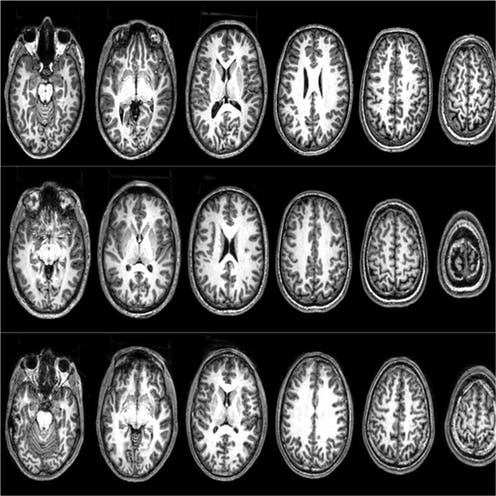

Brain scans from three ‘radicals’ who took part in the Barcelona studies. Brain scans from three 'radicals'. © Nafees Hamid and Clara Pretus, Author provided